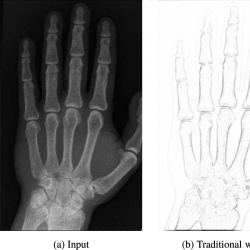

$k>0$ a contrast parameter. However, this inherits some of the drawbacks with other gradient regularizations such as detecting blocky edges, see Fig.

1(b). To improve the performance of the TV regularization and to avoid blocky artifacts, here we propose the following generalized inverse gradient term which incorporates local statistics with patches extracted from the image.

Fig. 1

Using an edge indicator based weights our adaptive TV regularization obtains better noise removal without smoothing out edges. (a) Input image with Poisson noise level unknown. (b) Weights computed using the inverse gradient of the input image, see Eq. (

5), and (c) the proposed generalized inverse gradient of the input image, see Eq. (

9), with parameters

$k=0.06$,

$r=5$,

$\sigma =1$. Both the weights were rescaled to

$[0,1]$ for better visualization.